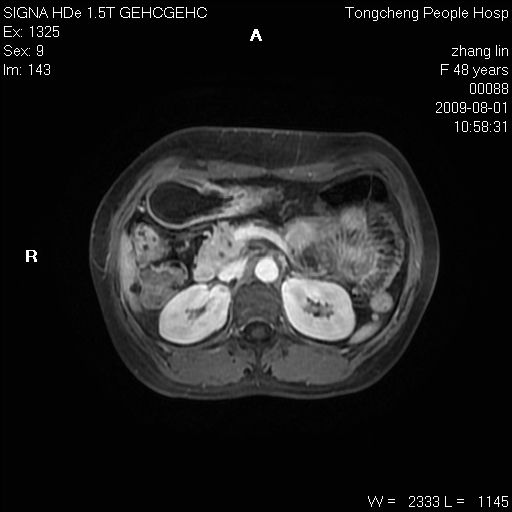

女,48岁。健康体检,彩超发现右肾占位性病变。平素健康。

临床诊断:右肾占位性病变,性质待定(囊肿?肿瘤?)。

上中腹部mr平扫+增强扫描,图像如下:

右肾上极见一类圆形病灶,t1wi呈等信号t2wi呈等高混杂信号,三期增强无强化,边界清---考虑囊肿出血。

同反相位均表现为等信号,病变无强化,考虑含蛋白的囊肿可能,弥散加权相或许有些帮助,

慢性胆囊炎